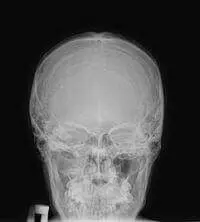

Для діагностики патології кісток черепа застосовуються в основному рентген і КТ. Найшвидшим і простим є рентгенографія черепа. Тому, при наявності скарг або при травмі, лікар насамперед призначає рентген голови.

- Оглядове дослідження – найпоширеніший метод, при якому видно структуру всього черепа (лобова кістка, лицьові кістки, потилична). У цьому випадку проводиться рентгенографія в 2-ух проекціях: прямій (в носо-лобному або носо-підборідному положенні) і бічний (бічна сторона голови притиснута до приймача рентген-апарату). Ці знімки призначають неврологи, нейрохірурги …